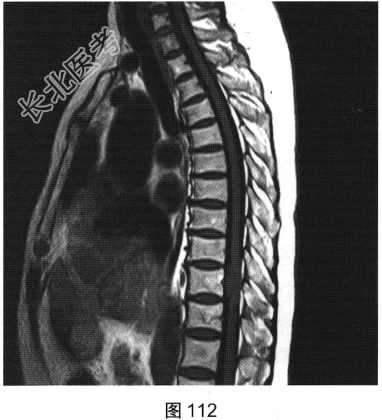

- [材料题] 患者女性,59岁,无明显诱因出现腰背部疼痛伴双下肢麻木1年,久行、久坐、久站或咳嗽、排便时疼痛加重,休息后症状缓解,1个月前腰背部麻木疼痛突发加重,行走100米既感疼痛难忍,伴双下肢无力疼痛。查体:脊柱无明显侧弯,相当于T10平面以下感觉减退,腰椎活动度受限,无紧张,棘突旁压痛、叩痛,向双下肢放射。挺腹试验阳性,跟臀试验(+),双侧直腿抬高试验(一),双下肢小腿外侧、足背感觉稍差,双侧

背伸肌肌力4级;肌张力正常,双侧巴宾斯基征可疑阳性。实验室检查:人类白细胞抗原B27阴性(一),RF<10U/ml(正常值0~15U/ml)。

- 多项选择题2.[提示]患者行MRI检查,如图111~图114所示。根据患者病史及影像学检查, 其最可能的诊断是( )